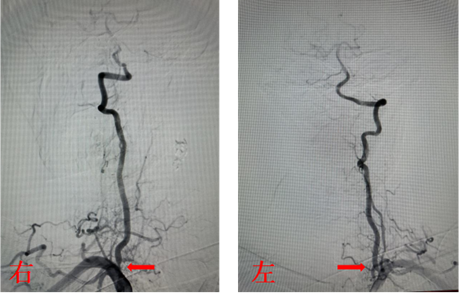

手术由神经内科孙奉辉主任和孙际典副主任医师实施,术中造影显示入颅的四条动脉(双侧颈内动脉起始部及双侧椎动脉开口)均有重度狭窄,尤其是右侧颈内动脉起始部为次全闭塞(如图),且为此次缺血性脑血管事件的责任血管,如不及时处理,病情可能随时加重。根据患者病情及家属诉求,决定先行右侧颈内动脉支架置入术,支架后血流恢复良好(如图)。术后患者症状完全消失,无明显不适。

双侧椎动脉开口重度狭窄